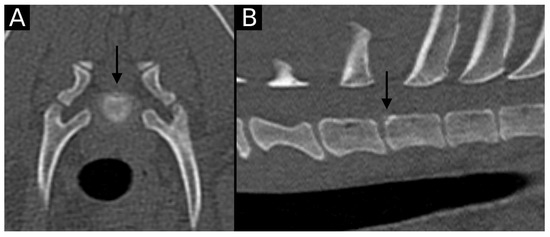

The junction between the endplates and intervertebral discs of the cervicothoracic junction (C6–C7, C7–T1 and T1–T2) were evaluated for the presence of alterations. When present, they were also graded and scored for EPJA, IVD herniation, spondylosis deformans, endplate sclerosis, articular process joint osteoarthrosis, and the presence of vertebral morphological abnormalities. The scoring system for endplate junction alterations and other spinal abnormalities was based on the proposed scoring by Tellegen et al. [13] for presumed EPJF at the lumbosacral spine. Endplate junction alterations were classified into four types (A, B, C, D): Type A involved presence of irregularity of the endplate margins without an obvious free fragment (Figure 1 and Figure 2); Type B involved avulsion evidenced by a thin rim of bone associated with a defect in the dorsal edge of the adjacent endplate (Figure 3); Type C included frank avulsion of a bony fragment (Figure 4) and Type D included presence of bony avulsion of both endplates. If EPJA was present, location (dorsal or ventral) and lateralization of the defect were also recorded. IVD herniation was graded from grades 0 to 3: grade 0 indicated no to mild (0–24%) herniation; grade 1 indicated mild to moderate (25–49%) herniation; grade 2 indicated moderate to marked (50–74%) herniation; grade 3 indicated marked herniation to complete obliteration (75–100%) of the vertebral canal by disc material. Spondylosis deformans was scored from grades 0 to 3: grade 0 indicated no enthesophytes; grade 1 indicated a small enthesophyte at the edge of the epiphysis that does not extend past the endplate; grade 2 indicated the presence of an enthesophyte that extends beyond the endplate but does not connect to the adjacent vertebra; and grade 3 indicated connecting enthesophytes from adjacent vertebrae forming a mineralized bridge. The other mentioned abnormalities (IVD mineralization, endplate sclerosis and articular process joint osteoarthrosis) were scored as present (1) or absent (0).

Figure 2. Transverse (A) and sagittal (B) reconstructions in bone algorithm. Mild contour irregularity and flattening lined by mild sclerosis are observed at the dorsal aspect of the T1 cranial endplate (arrow), consistent with EPJA Type A.